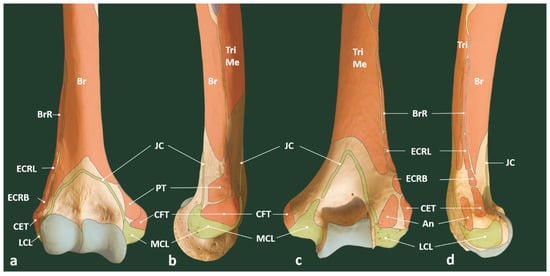

3.1. Tennis Elbow

3.1.1. Essential Anatomy